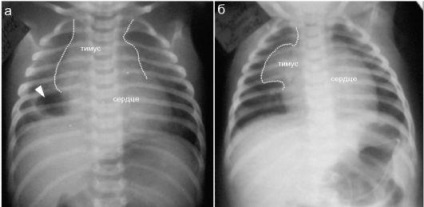

diagnózis thymomegaly

Thymomegaly fejlettségű gyermekek definíciója szerint attribútumok (megjelenés a rák röntgen), és az eredményeket a speciális méréseket.

Minőségi jellemzői diagnosztizálására fokú felbontás thymomegaly thymus árnyéka a röntgenfelvételen. A kezelési rend választjuk szigorúan egyénileg, attól függően, hogy a betegség, az általános állapot, az immunrendszer és a súlyosságát a gyermek életkora.